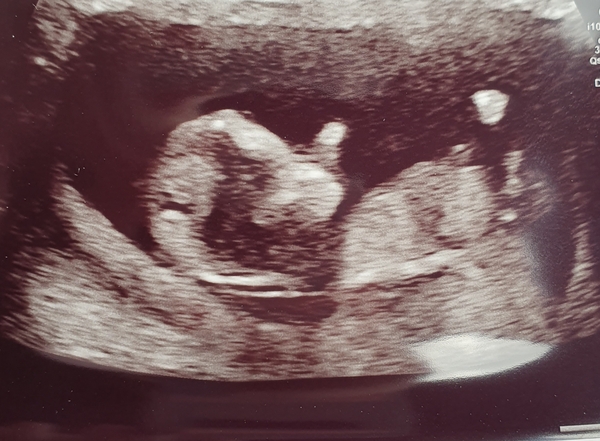

Hi, I just wondered if anyone had been able to video call or film some of their antenatal scans at the hospital for their partner? Due to covid19 I have to go alone , it's not my first but it's our first together.I called the unit and they said to ask the person carrying out the scan, I just wondered what other peoples experiences of this was and wether they had been able to film or call?